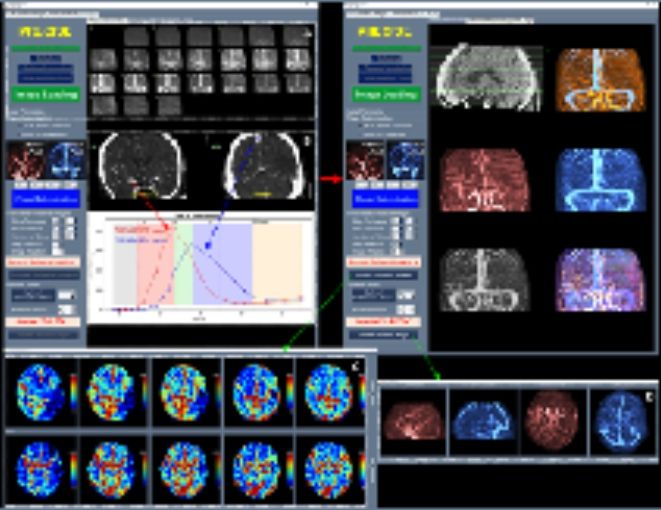

이와 함께 허혈성 뇌혈관 질환 환자를 대상으로 혈관재개통 치료가 필요한 환자 선별을 지원하는 소프트웨어 등 다양한 진단·치료 보조 AI 의료기기들이 혁신의료기기로 지정됐다.